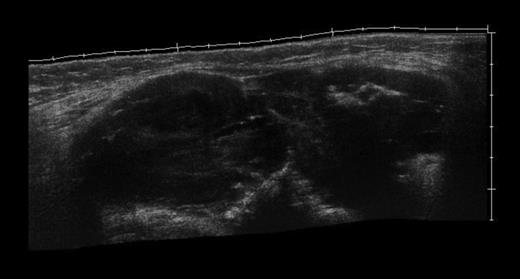

An ultrasound scan (Fig. 1) revealed a large mass lesion with heterogeneous appearances in the popliteal fossa extending between the two heads of the gastronemii and large blood vessels in the central region of the mass. It measured ∼13 × 5.5 × 4.5 cm in dimension and a magnetic resonance imaging (MRI) scan was suggested to rule out mass arising from the popliteal vessels being enveloped by the mass.

Ultrasound image showing heterogenous mass between the two heads of gastrocnemius muscle.